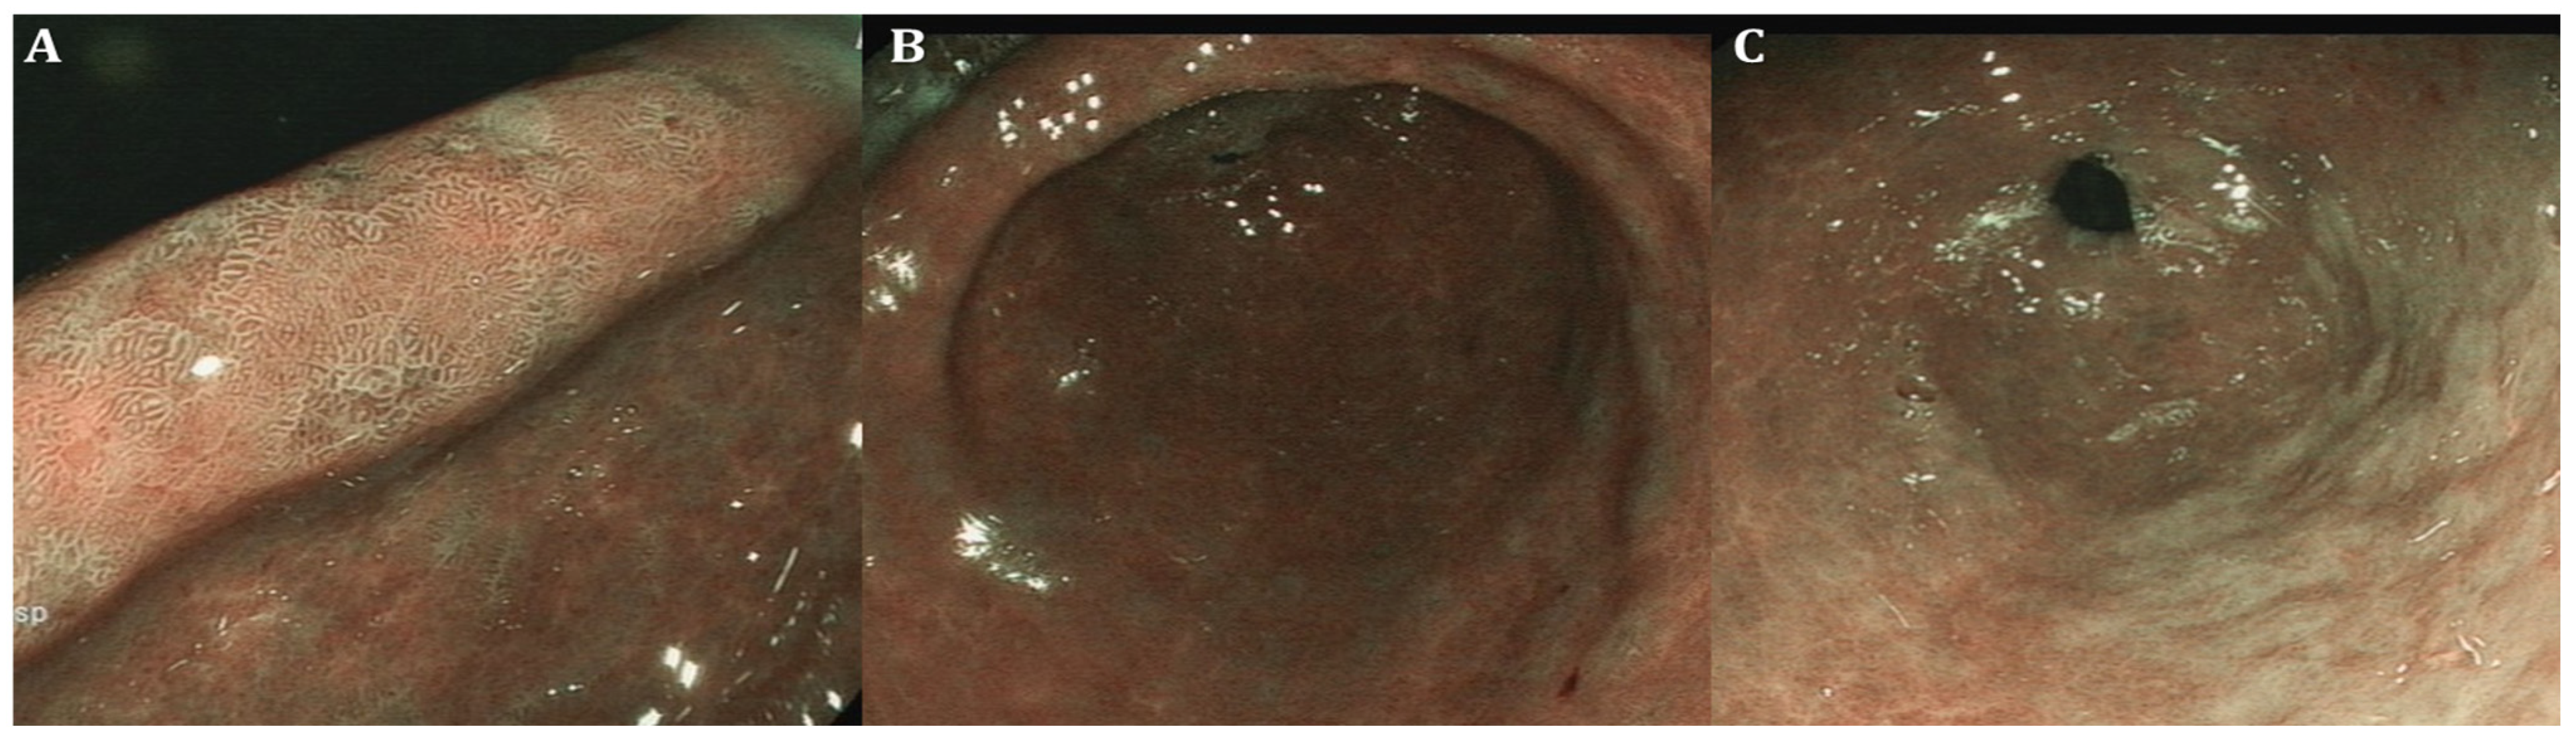

| GIM endoscopic findings | Light-blue crest (LBC) as fine blue–white line on the crest of the epithelial surface, white opaque substance (lipid droplets) obscuring the subepithelial capillaries, multiple pale, elevated patches | Elevated greyish white patches surrounded by pale and normal-color gastric mucosa or blotchy patchy erythema, lipid droplets termed white opaque substance (WOS), patchy reflections of blue–white located on epithelial margins termed light-blue crest | Lavender area, “Lavender color sign” (LCS); “Purple in Mist” (purple mixed with white on the epithelium, with signs of mist detected by non-magnifying LCI observation—PIM); “patchy lavender color” (patchy lavender color with a regular mucosal pattern and a clear border—PLC) |